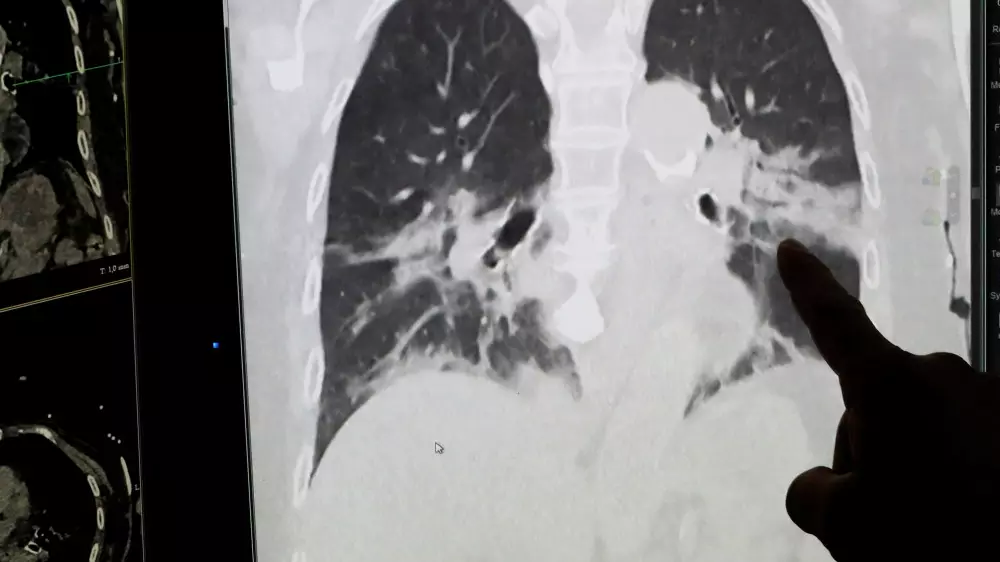

Наряду с выяснением ранее перенесенных заболеваний патологоанатомы также изучили повреждения легочной ткани умерших.

"Воспаление легких было у наименьшего числа пациентов. Под микроскопом мы увидели тяжелое нарушение микроциркуляции в легких", - сообщил Цанков.

Это, по его словам, означает, что кислородный обмен больше не функционировал, и объясняет трудности при искусственной вентиляции легких пациентов с COVID-19 в отделениях интенсивной терапии. "Можно дать пациенту столько кислорода, сколько хочется, он просто не транспортируется дальше", - пояснил профессор.